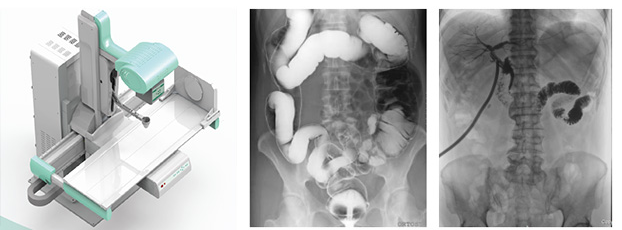

DR是數(shù)字化直接成像系統(tǒng)的簡(jiǎn)稱,也常寫作Dr,是指在計(jì)算機(jī)控制下直接進(jìn)行數(shù)字化X線攝影的一種新技術(shù),即采非晶硅平板探測(cè)器把穿透人體的X線信息轉(zhuǎn)化為數(shù)字信號(hào),并由計(jì)算機(jī)重建圖像及進(jìn)行一系列的圖像后處理。那動(dòng)態(tài)DR是什么DR呢?從其宣傳看首先它是個(gè)DR,可以做數(shù)字?jǐn)z影,其次它可以透視點(diǎn)片,可以進(jìn)行消化道造影及泌尿系統(tǒng)造影,并可以進(jìn)行治療引導(dǎo)。

動(dòng)態(tài)DR可以從不同的角度、時(shí)間來(lái)觀察器官的運(yùn)動(dòng),診斷準(zhǔn)確率會(huì)大大提升。其實(shí)動(dòng)態(tài)DR的多角度檢查,其視覺(jué)效果上有點(diǎn)類似于CT。

動(dòng)態(tài)DR所采用的數(shù)字探測(cè)器,全幀技術(shù)可以得到盡量大的光電二極管,能夠輸出更穩(wěn)定清晰的影像質(zhì)量。數(shù)字高壓技術(shù)具有高壓快門,能夠在毫秒級(jí)時(shí)間內(nèi),實(shí)現(xiàn)高壓的切換。采用雙通道算法以及并行圖像處理技術(shù)。動(dòng)態(tài)dr的探測(cè)器為17*17 ,完全可以在同一個(gè)屏幕中獲取整個(gè)檢查部位的視野,便于觀察。

其次采用動(dòng)態(tài)dr視頻采集技術(shù),經(jīng)過(guò)一次順利的檢查后保存視頻,可以實(shí)時(shí)回顧分析采集圖像,也有利于疾病的隨訪、對(duì)比及會(huì)診。此外,在骨科診斷過(guò)程中,由于隱匿性骨折范圍小、程度輕,即使使用ct檢查敏感性也不高,mri檢查費(fèi)用過(guò)于昂貴,而用動(dòng)態(tài)DR透視下的多軸位點(diǎn)片,可以明確隱匿性骨折的診斷,是避免誤診隱匿性骨折的有效辦法之一。

動(dòng)態(tài)DR對(duì)某些重疊病灶的診斷有著極高的臨床意義,在常規(guī)DR所拍攝的靜態(tài)片中很難區(qū)分重疊病灶是處在什么位置及哪個(gè)器官上,而通過(guò)動(dòng)態(tài)觀察可以清晰的判斷和診斷。